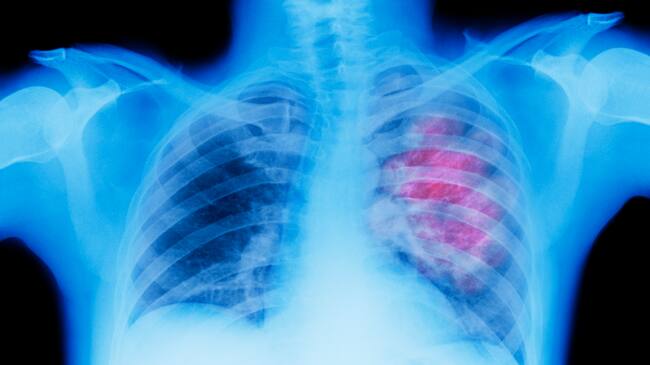

Imagen de referencia. Foto: Getty Images / Peter Dazeley

La especialista explicó que el cáncer de pulmón se consolida como la principal causa de muerte oncológica a nivel mundial, el cual en Colombia ha mostrado un incremento alarmante. Aunque históricamente ha sido la principal causa de muerte en hombres, también ocupa el segundo lugar en mujeres.

Si bien el factor de riesgo más significativo es el consumo de tabaco, que se asocia directamente con el 85% de los casos de cáncer de pulmón, existen otras variables que merecen igual atención, muchas de las cuales son controlables y contribuyen a la preocupación sobre la salud pulmonar.